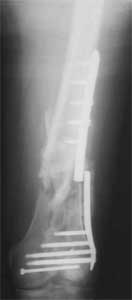

Attached are few examples from our Hospital:

A. Difficult reductions, even in retrograde nailing (my preference, easier control of "small" distal fragment) and it is much, much harder to do it anterograde (Alex, do you have one good case in your collection of anterograde nailing in very distal fractures - as you have suggested that I

should have done it in my previously posted case?

Malpositioning is much too common (recurvatum, varus - valgus).

B. Fixation loosening: distal cutting of the nail, non-unions do happen (cases attached).

Locking Plating has more distal screws than any nail, fixed angles and provides much better fixation, especially in osteoporotic bone.